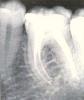

Inviolable Опубликовано 7 августа, 2008 Автор Поделиться Опубликовано 7 августа, 2008 Вчера наконец то поговорила с главврачем, еще раз сделали снимки, которые ниже прикрепляю. Его диагноз меня совсем не порадовал, поскольку он настаивает на разрезе десны, чтобы прочистить канал, потому что через зуб это сделать уже невозможно. Посмотрите пожалуйста, я все еще надеюсь, что возможно он ошибся (он кстати тоже просил другому специалисту показать снимки). На всякий случай два снимка с разницей в неделю, хотя там вобщем то одно и тоже. Ссылка на комментарий

Inviolable Опубликовано 7 августа, 2008 Автор Поделиться Опубликовано 7 августа, 2008 снимок очень яркий, не видно ничего.но мне кажется или гуттаперча за верхушкой? Да, скорее всего, по крайней мере так сказал мне врач, и поэтому надо резать десну и чистить, потому что пломба уже как каменая и они достать через зуб не могут А нет ли какого другого способа, не хирургического? Ссылка на комментарий

Bier Опубликовано 7 августа, 2008 Поделиться Опубликовано 7 августа, 2008 резать и делать резекцию я смысла не вижу, болевой синдром проходит и судя по всему пройдет окончательно сам. Выведенная за верхушку гуттаперча - не самая большая проблема, она инертна и сама по себе не вызовет никаких осложнений. Ссылка на комментарий

Zlata-doctor Опубликовано 7 августа, 2008 Поделиться Опубликовано 7 августа, 2008 резать и делать резекцию я смысла не вижу, болевой синдром проходит и судя по всему пройдет окончательно сам. Выведенная за верхушку гуттаперча - не самая большая проблема, она инертна и сама по себе не вызовет никаких осложнений. Поддерживаю полностью. Сделайте контрольный снимок даже при отсутствии болей через 6 мес, потом можно через год и сравнить их. Ссылка на комментарий